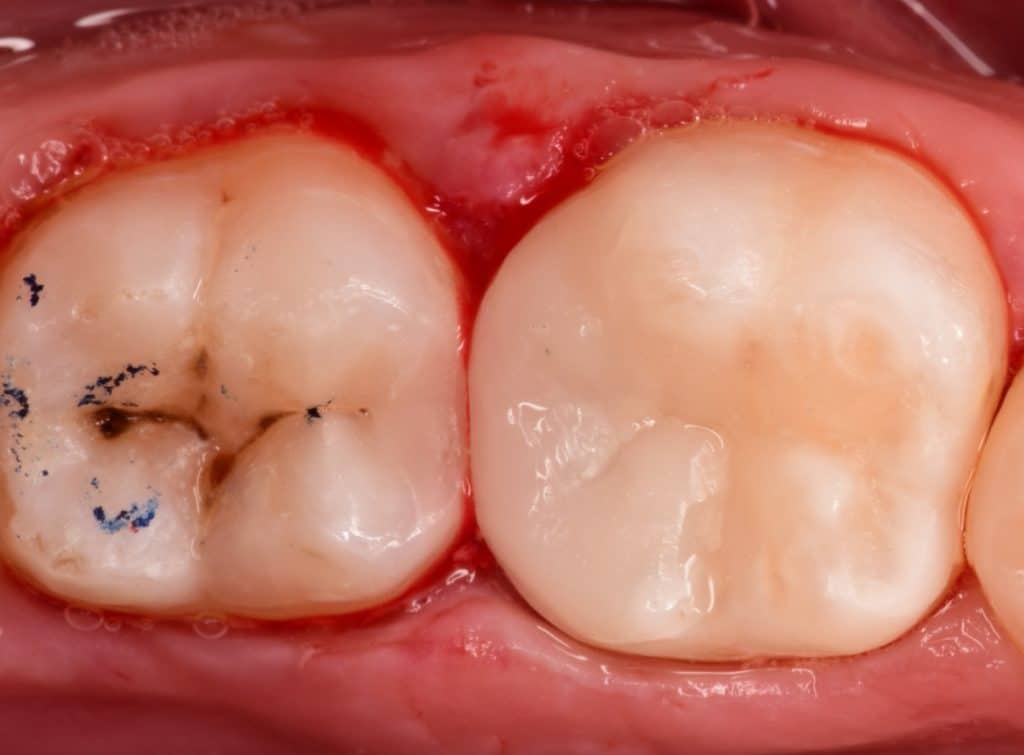

Isolation as first step

Buccal view showing the depth of the cavity of the #6 and slo the mesail wall of the second molar with Initial caries need to prepared

Buccal view showing the two cavities are cleaned, sharp edge need to be removed